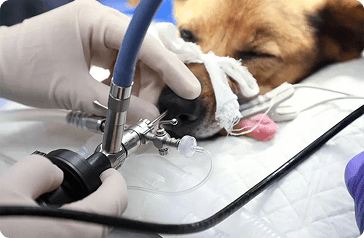

Endoszkópia

Az endoszkópia az üreges belső szervek, testüregek optikai eszköz segítségével történő vizsgálata. Leggyakrabban az orrjáratok és emésztőrendszeri idegentestek eltávolítása, daganatos elváltozások mintavételezése és a külső hallójárat vizsgálata, mintavételezése a feladat.